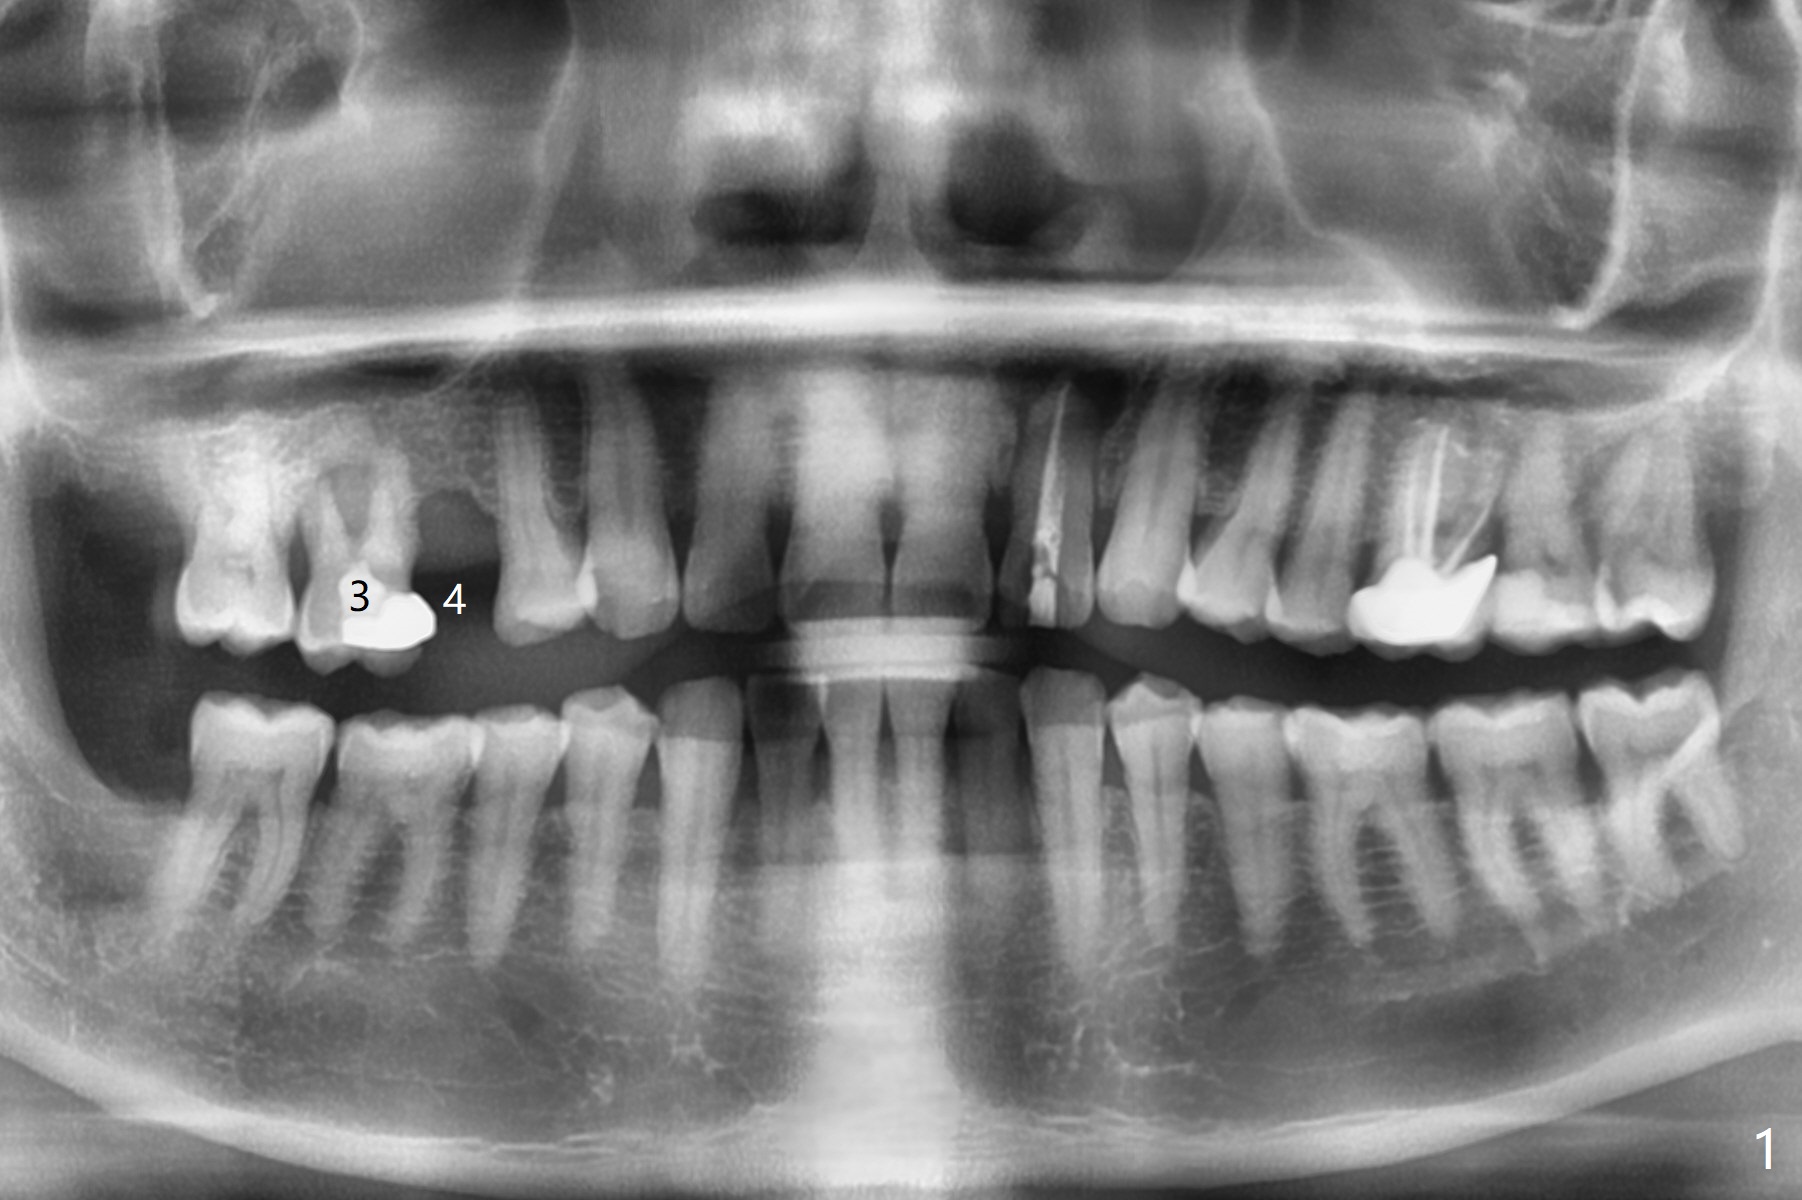

A 49-year-old man (patient of ours for 7 years) has severe bone loss and buccal recession at #3 with missing tooth at #4 (Fig.1,2,5). Short implants will be placed as palatal as possible (Fig.3,4 green) with buccal bone graft (red circles). PRF will be prepared for membranes and sticky bone.